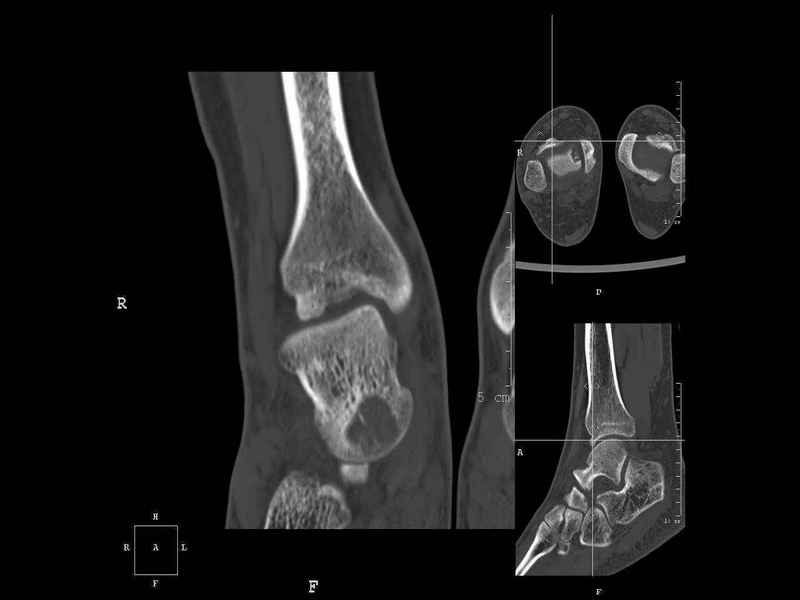

Рассекающий остеходрит + киста шейки тарана

Уважаемые коллеги, обратился за помощью пациент, мужчина, 25 лет. С жалобами на болевой синдром в области голеностопного сустава и среднем отделе стопы.

Травму отрицает. Со слов, болевой синдром в течении 1 года. Последние 1-1.5 мес периодически вынужден пользоваться костылями. После ограничения нагрузки боли уменьшаются. Соматически здоров. До появления болей активно занимался рукопашным боем.

На СКТ картина рассекающего остеохондрита блока таранной кости, киста шейки таранной кости с признаками импрессии суставной поверхности. А также - разрастания переднего края б\берцовой кости сопровождающиеся клиникой импиджмент синдрома.

Предполагаемый план лечения- удаление свободного фрагмента суставного хряща из трансмаллеолярного доступа с рассверливанием поверхности дефекта, кюретаж кисты шейки с заполнением полости биокомпозитом + дебридмент переднего отдела голеностопного сустава.